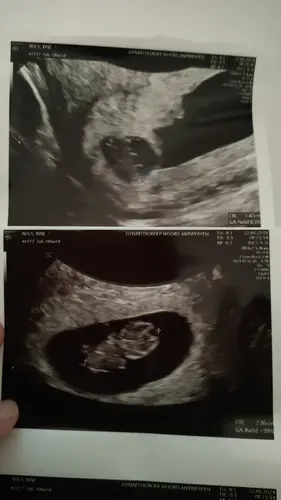

Hier ook een echo van rond de zes weken. Baby 2 is de hele zwangerschap kleiner gebleven. Maar ondertussen zijn onze meisjes 11 maanden oud en moet baby 2 zeker al lang niet meer onder doen, integendeel 😉.

Hier ook een tweeling waarvan eentje de hele zwangerschap kleiner is geweest. Bij de eerste echo rond 6 weken waren ze 0,85 en 1,17 cm. Ook bij de geboorte was er een groot verschil in gewicht (2080 en 2720g) maar ze zijn allebei perfect gezond.